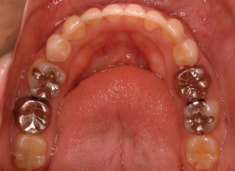

治療後(2年5ヶ月後)

治療開始から約1年2ヶ月後